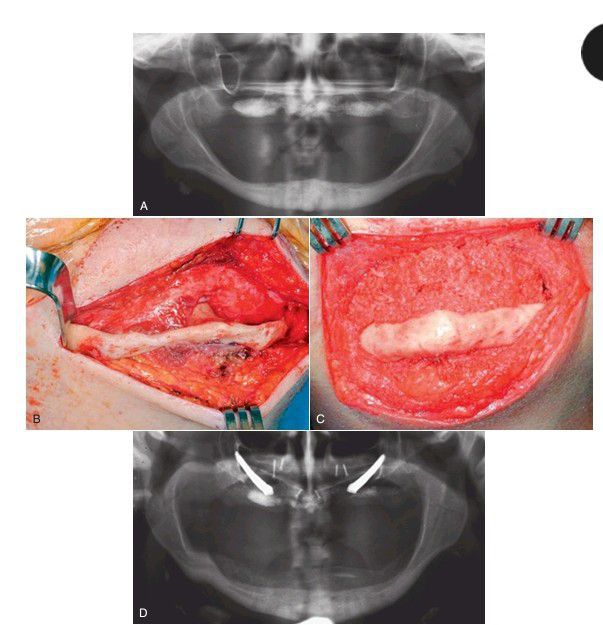

(A) Preoperative radiograph. (B) Exposure of atrophic mandible through an extraoral approach. (C) Bone graft in place. Bone graft was a combination of bone morphogenetic protein, stem cells harvested by aspiration of iliac crest marrow, and freeze-dried bone. (D) Six-month postoperative radiograph. (Maxillary bone graft and zygomaticus implants were placed at the time of mandibular grafting.) Note that the bone graft area is not as dense as underlying bone. When implants are placed and stress is applied to grafted bone, the de